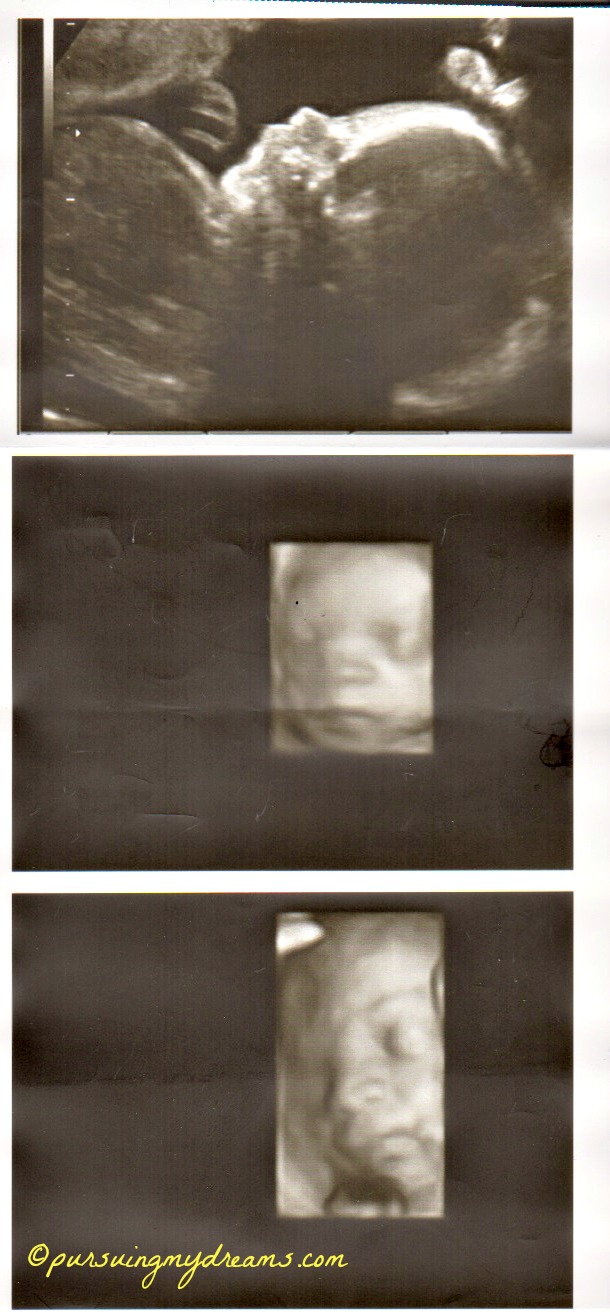

Sebagai penutup saya sertakan foto hasil usg anakku. Ini usg saat usia kehamilan 25 minggu. Dilakukan di kliknik Mannheim. Setelah itu sampai saat ini dokter tidak pernah melakukan pemeriksaan usg lagi karena semuanya baik-baik saja. Jadi hanya diperiksa posisi kandungan.

yang 2x karena aku ada pemeriksaan di klinik yg lebih besar Cha trus dikasih print out USG nya, klo di dokter biasa cuma 2x ga dikasih print out usgnya 😥 .

Mending mbak 3x disini kl hamilnya normal, mksdku gak melalui IVF kaya’nya cm 2x deh USG nya udh gt ya yang 2D itu doank, itu 4D kan mbak yah?? 36 mgg gak terasa ntar lagi bertiga deh kaliaaaan… Semoga sehat dan lancar ampe lairannya ntar ya mbak :*

Aku sdh 36 minggu nih. USG cuma 3 kali 🙁 pelit dokternya pdhl tiap kali ke dokter aku semangat pengen lihat si kecil kan.

Iya bang keliatan jelas, padahal itu masih 25 minggu. Ga tau saya usg apa namanya hehehe.

Hidung anakku ngikut aku Ndang alias pesek, dokternya bilang gitu 😆 .